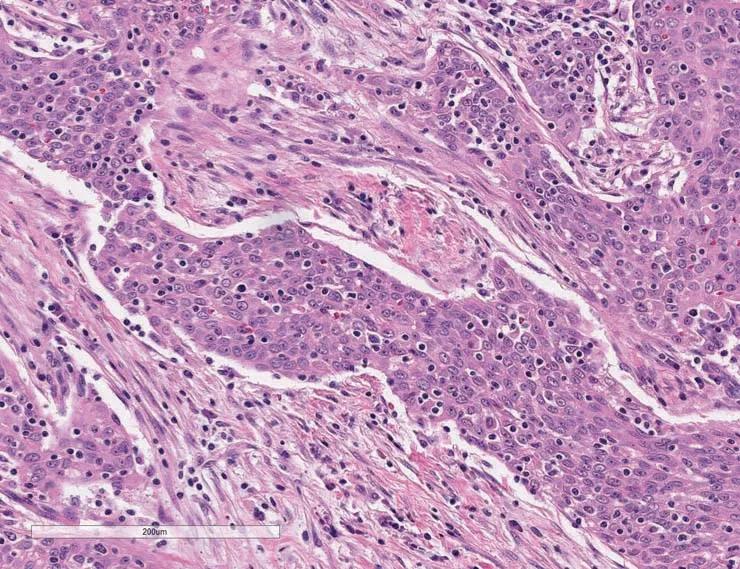

Low-passage samples retain the heterogeneity and fidelity of human cancers. Engrafted tumors derived from a patient with a bladder urothelial papillary carcinoma demonstrate high concordance of tumor morphology, compared to low passage PDX tumor TM00015.

Figure A) Histology from the patient's primary tumor: High-grade urothelial carcinoma invading the bladder wall.

Figure B) Once engrafted, the histology for PDX model TM00015 at passage 1 also corresponds to high-rate urothelial carcinoma.